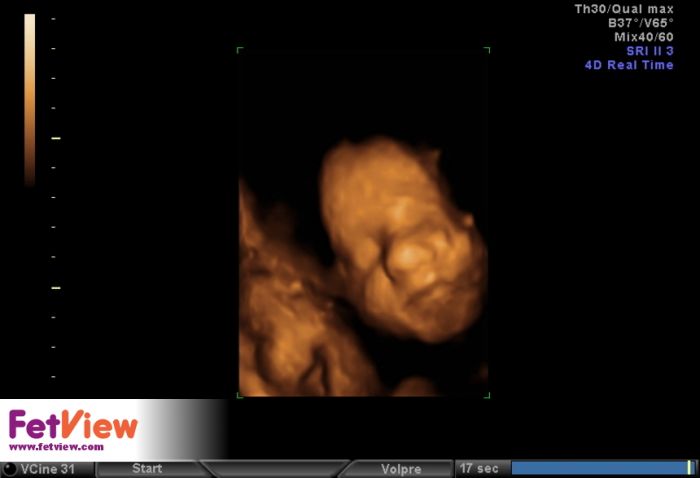

Ahoj všem, tak dnes mám po další kontrole 28+4 a vše odpovídá :-) maličká je v pořádku, je to pořád holka a dneska se i chtěla ukazovat :-) vyplazovala na nás dokonce i jazyk :-) má 1323g, zatím je položená zadečkem dole, ale prý je ještě spousty času aby se otočila. Doktor se divil, že na svou váhu mám super výsledky z cukrovky, že se to moc nestává, čípek zavřený, otoky nikde. Příští týden jdu ještě k obvoďákovi na ekg a pak ještě jednou zubař a kolečko mám snad kompletní - hurááá!

Slonice gratuluji, hezká fotečka :)